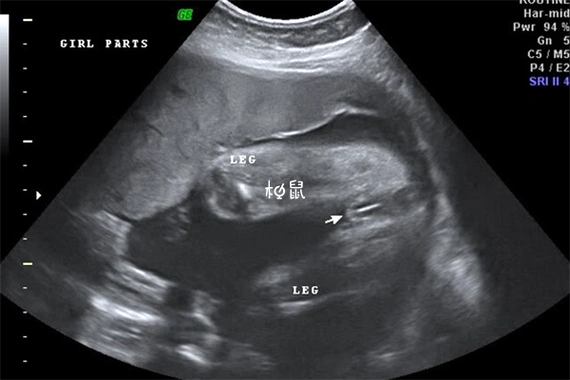

怀女宝孕囊,长是宽的两倍,准吗?

三条线是男孩还是女孩

通过b超图像看男女,经过大量妈妈验证,特别准